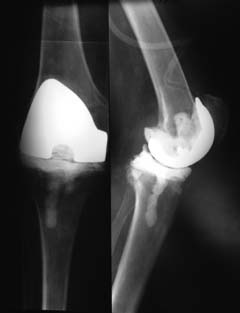

Уважаемые коллеги! Пациент мужчина 62 года, эндопротезирование коленного сустава в сентябре 2011 в одном из соседних учреждений. Множественные операции по восстановлению связок в анамнезе.

Под наше наблюдение попал спустя 3 месяца с клиникой глубокой перипротезной инфекции. Гнойный свищ, MRSA в посеве. Выполнено удаление протеза, некрэктомия, установка цементного спейсера. Заживление первичное, а\б терапия по посевам, в течении 2 месяцев положительная динамика, нормализация лабораторных показателей. В последующем усиление болей, отек, разрушение спейсера по рентегнограммам. Взят в операционную для повторной некрэктомии, удаления спейсера. Во время операции выявлено- отсутствие явного гнойного содержимого, ткани более жизнеспособные, чем во время первого удаления, отсутствие значительного прогрессирования костных дефектов. Решено от одномоментного артродеза воздержаться, конечность стабилизирована дистракционным аппаратом. В интраоперациооных посевах St.aureus. В настоящее время две недели после операции, встает вопрос о возможностях далнейшего лечения. Ревизонное колено? Еще раз после спейсера или сразу? Или артродез?